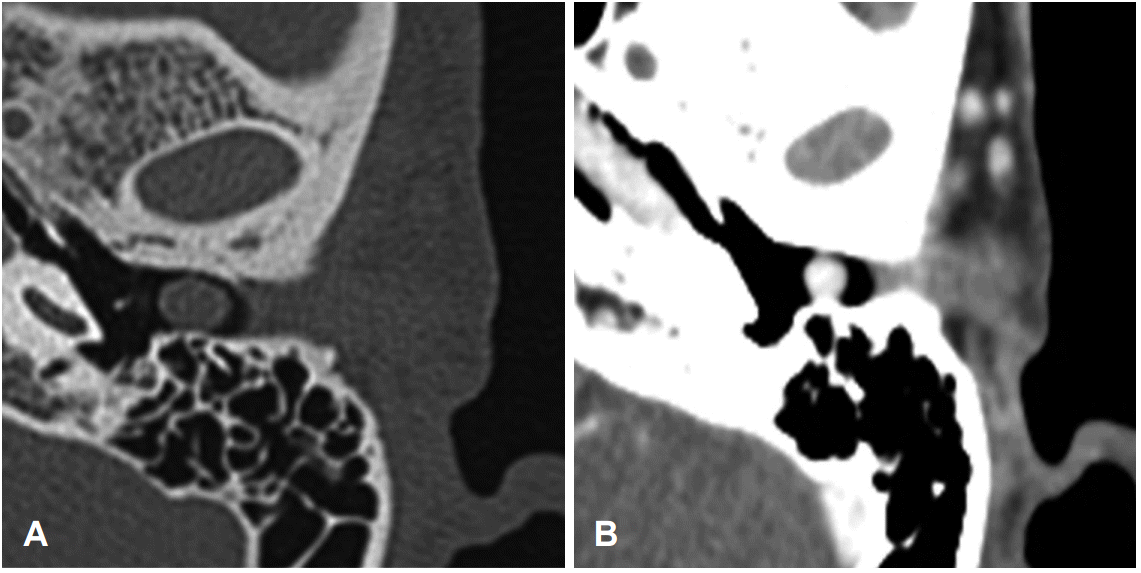

측두골 전산화단층촬영에서 좌측 외이도에 경계가 비교적 분명한 연부조직 음영의 종물이 고막과 접하여 관찰되었으나 중이나 골성 외이도로의 침범은 없었다(Fig. 3). 자기공명영상에서는 T1 강조영상에서 종물이 혈관과 비슷한 정도의 조영증강을 보이고 있어 혈관종과 같은 혈관분포가 높은 종물로 판독되었다.

Fig. 3.

Preoperative temporal bone axial (A) and enhanced (B) CT scans demonstrate a soft tissue lesion in the external auditory canal.

이학적 검사에서는 이내시경상 특징적으로 표면이 매끄럽고 모양이 둥근 적색의 종물로 관찰되므로 쉽게 진단이 가능하다[6,8,10]. 혈관종의 병변 범위의 확인에 있어서는 측두골 전산화단층촬영이 가장 좋은 영상진단검사[11]이며, 외이도에 비정상적인 연부조직 음영이 특징적인 소견이다. 본 증례에서도 측두골 전산화단층촬영에서 좌측 외이도에 경계가 비교적 분명한 연부조직 음영의 종물이 보였으며 골성 외이도나 중이로의 침범은 없는 것을 수술 전에 확인할 수 있었으며 추가적으로 시행한 자기공명영상에서도 좌측 외이도에 T1 강조영상에서 종물이 혈관과 비슷한 정도의 조영증강을 보이고 있어 혈관종과 같이 혈관분화가 높은 종물로 판독할 수 있었다.